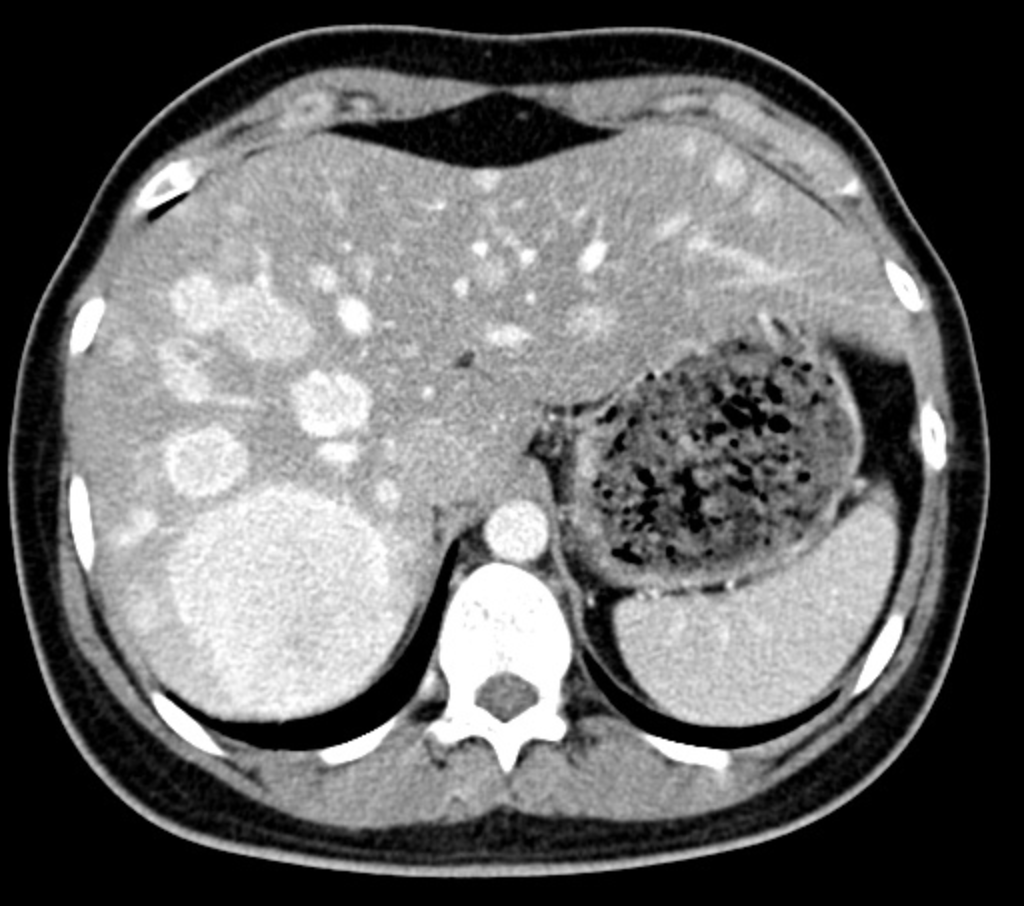

#idboardreview 35 M PLWH CD4 10, VL >200k presents w/ fever and myalgias x 1mo. CT w/ hypodense lesions, biopsy with 'blood lake'. Warthin-Starry stain+ diagnosis? #idmedEd #medEd #IDtwitter ImageImage

hepatosplenic #bacillary #peliosis #bartonella #henselae “blood lake” due to vascular dilation mixed with focal bleeding, numerous bacilli on WS stain or immunostaining

#Peliosis #hepatis rare condition characterized by tumor-like liver lesions composed of multiple blood-filled cavities. Associated with cytotoxic drug, gamma-ray, bacterial or viral infection, immunodeficiency etc

#Bacillary #peliosis #hepatis, a vascular lesion of the liver associated with infiltration of #Bartonella bacilli,1st described in eight HIV-infected individuals by Perkocha. Presents w/ abdominal pain and fever.

25% patients with #peliosis #hepatis also have cutaneous #bacillary lesions. Serum AlkP more prominently elevated than the hepatic transaminases